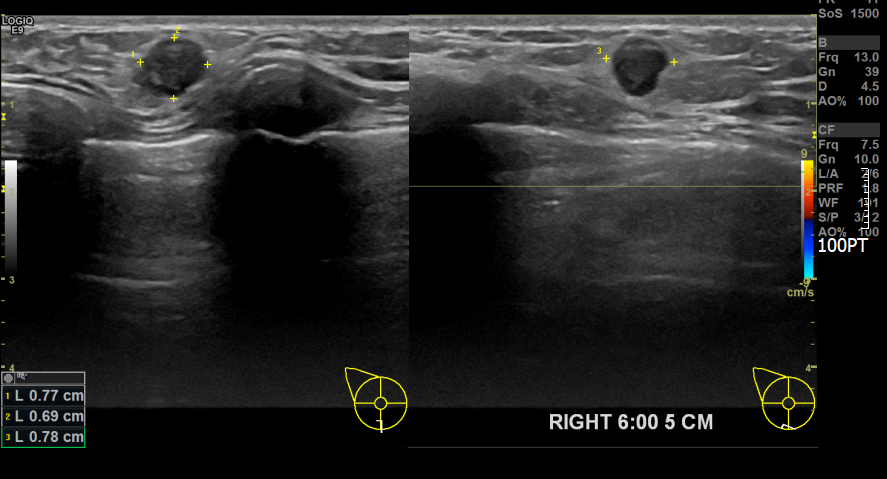

아산유외과 개원후 751번째 유방암진단

상기환자 외부검진상 이상소견으로 내원해주신 40대여성분으로 의심스러운혹 조직검사시행후

유방암진단되셨습니다.